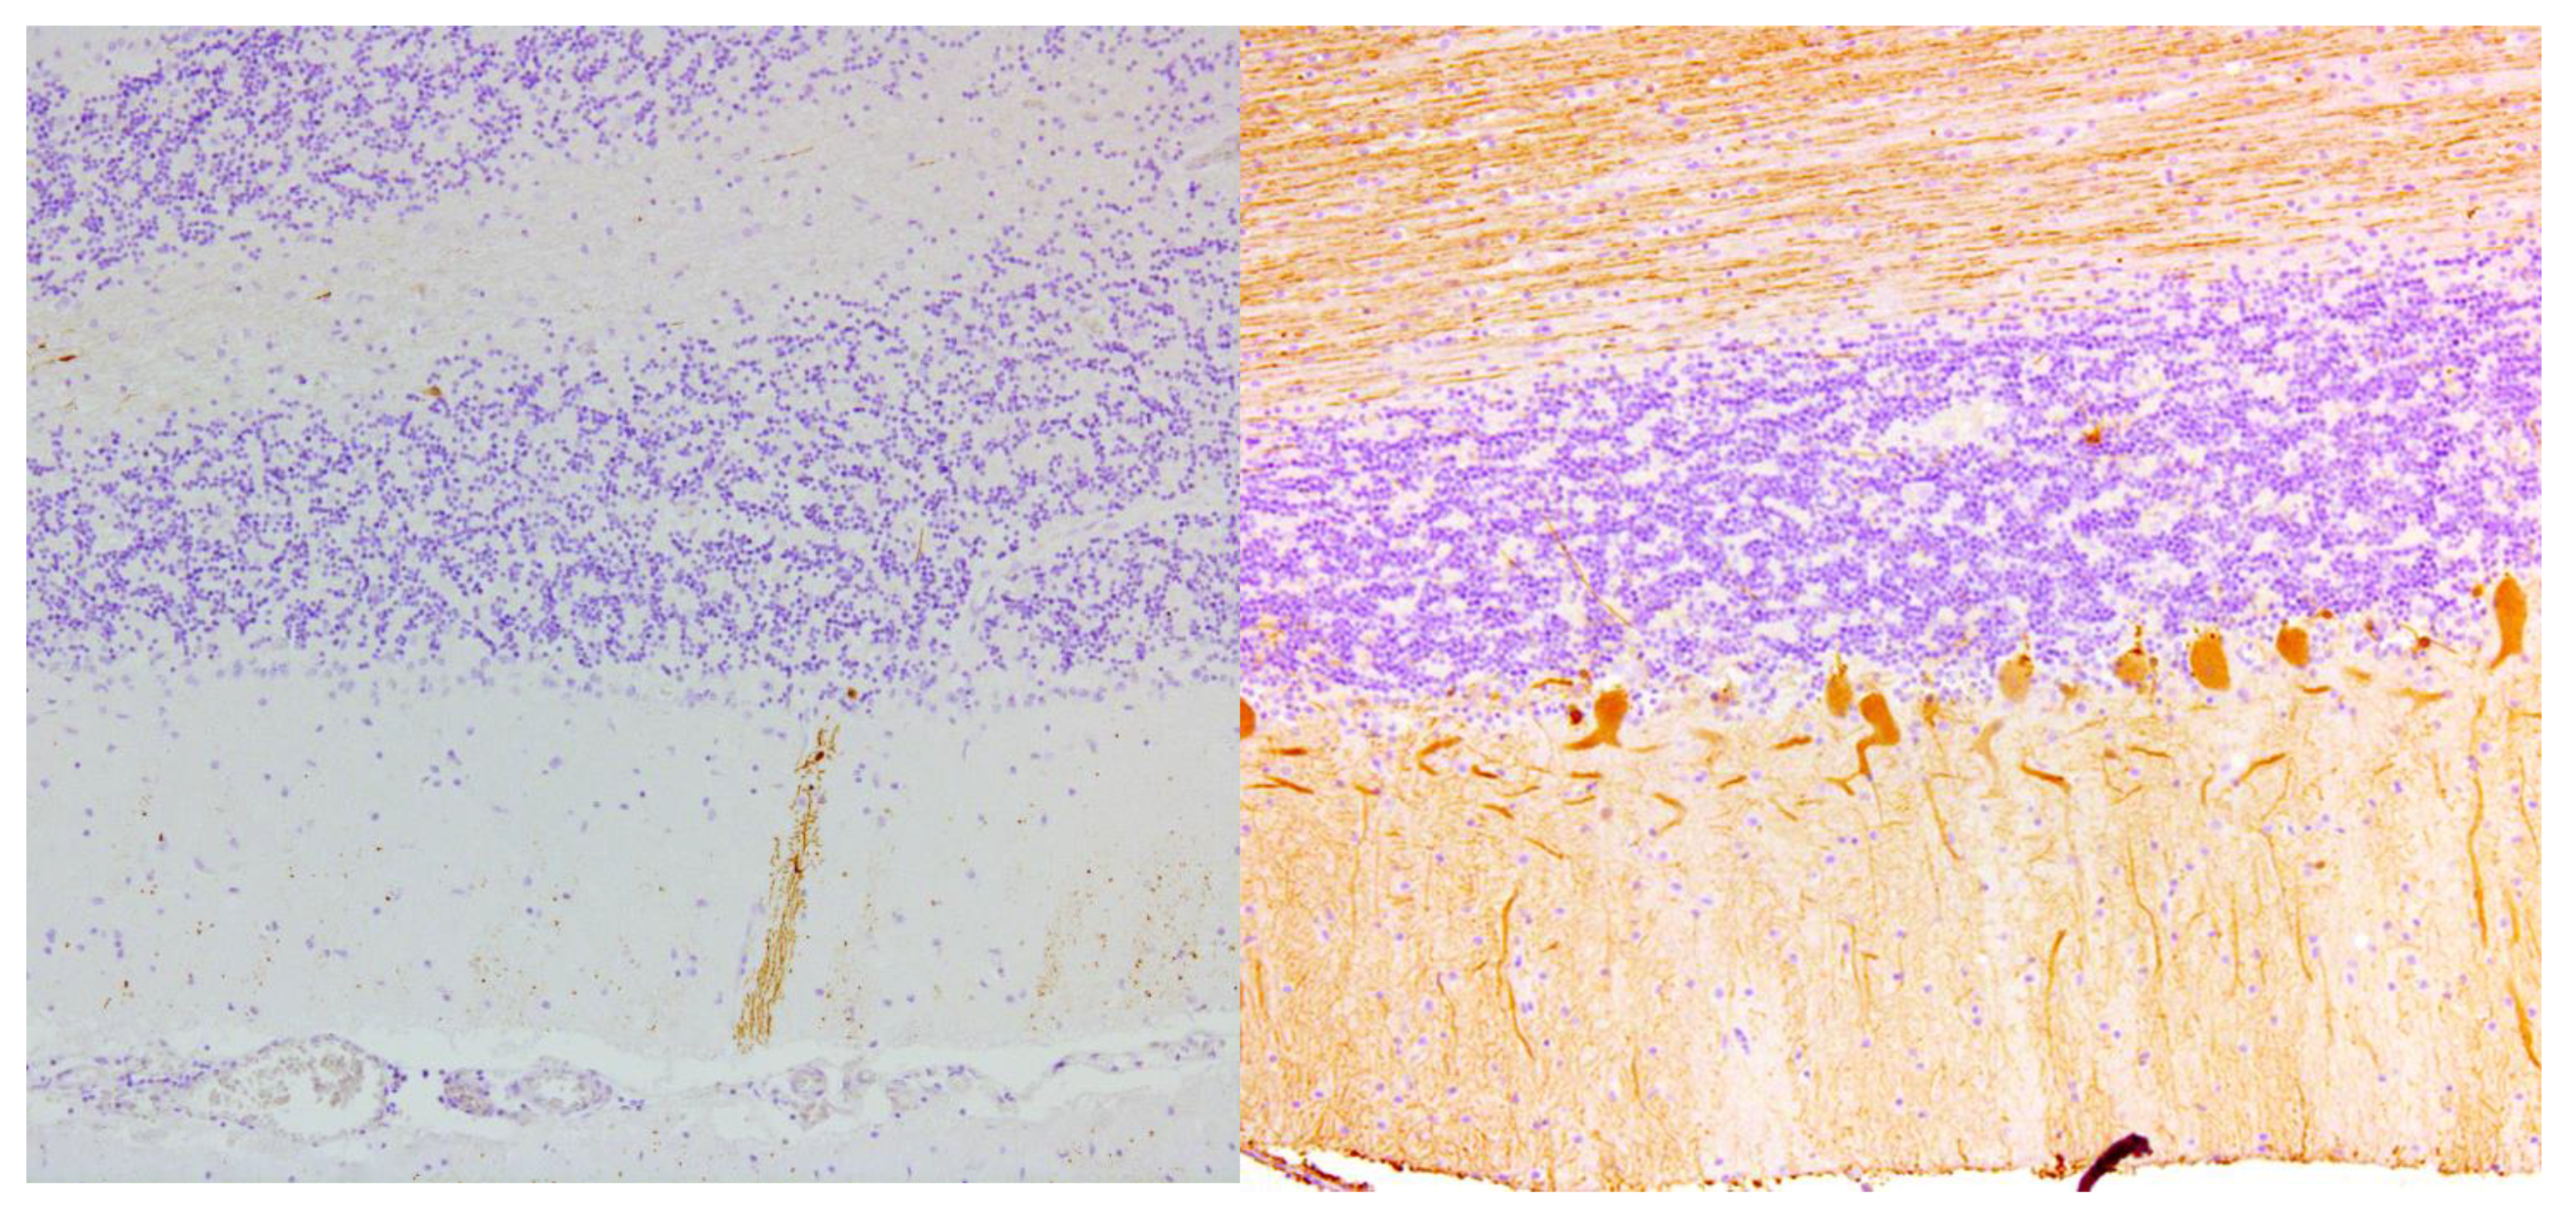

| Hadjivassiliou 1998, UK | 2 | Brain Spinal cord | Loss of Purkinje cells; Cerebellar atrophy & astrocytic gliosis & vacuolation of neutrophils; Diffuse infiltration of lymphocytes & perivascular cuffing of T-lymphocytes in the cerebellum and the post. columns |

| Hadjivassiliou 2006, UK ** | 1 | Brain | Capillary changes in the white matter, hippocampus and olives marked by vascular and perivascular inflammatory cell infiltrates (CD68+ cells and a smaller CD45Ro+ cell population). Purkinje cell loss and Bergmann gliosis and loss of neurons in the inferior olives |

| Mittelbronn 2010, Germany | 1 | Brain | Loss of Purkinje cells & cerebellar granular layer cells; Cerebellar atrophy and astrocytic gliosis; Severe neuronal loss inferior olives & accumulation of corpora amylacea. Cerebral reactive astrogliosis and microglial activation Inflammation dominated by CD8+/granzyme B+ & CD20-/CD138- diffuse infiltrates & perivascular cuffing in the cerebellum and brainstem |

| Nanri 2011, Japan | 1 | Brain | Loss of Purkinje cells; Minimal cerebellar atrophy; Mild Bergmann gliosis. Empty basket cells, Edematous splitting of Purkinje cell layer, loss of granular cells. No lymphocytic infiltration (CD3-, CD4-, CD8-, CD20-, CD68-, CD79A-) |